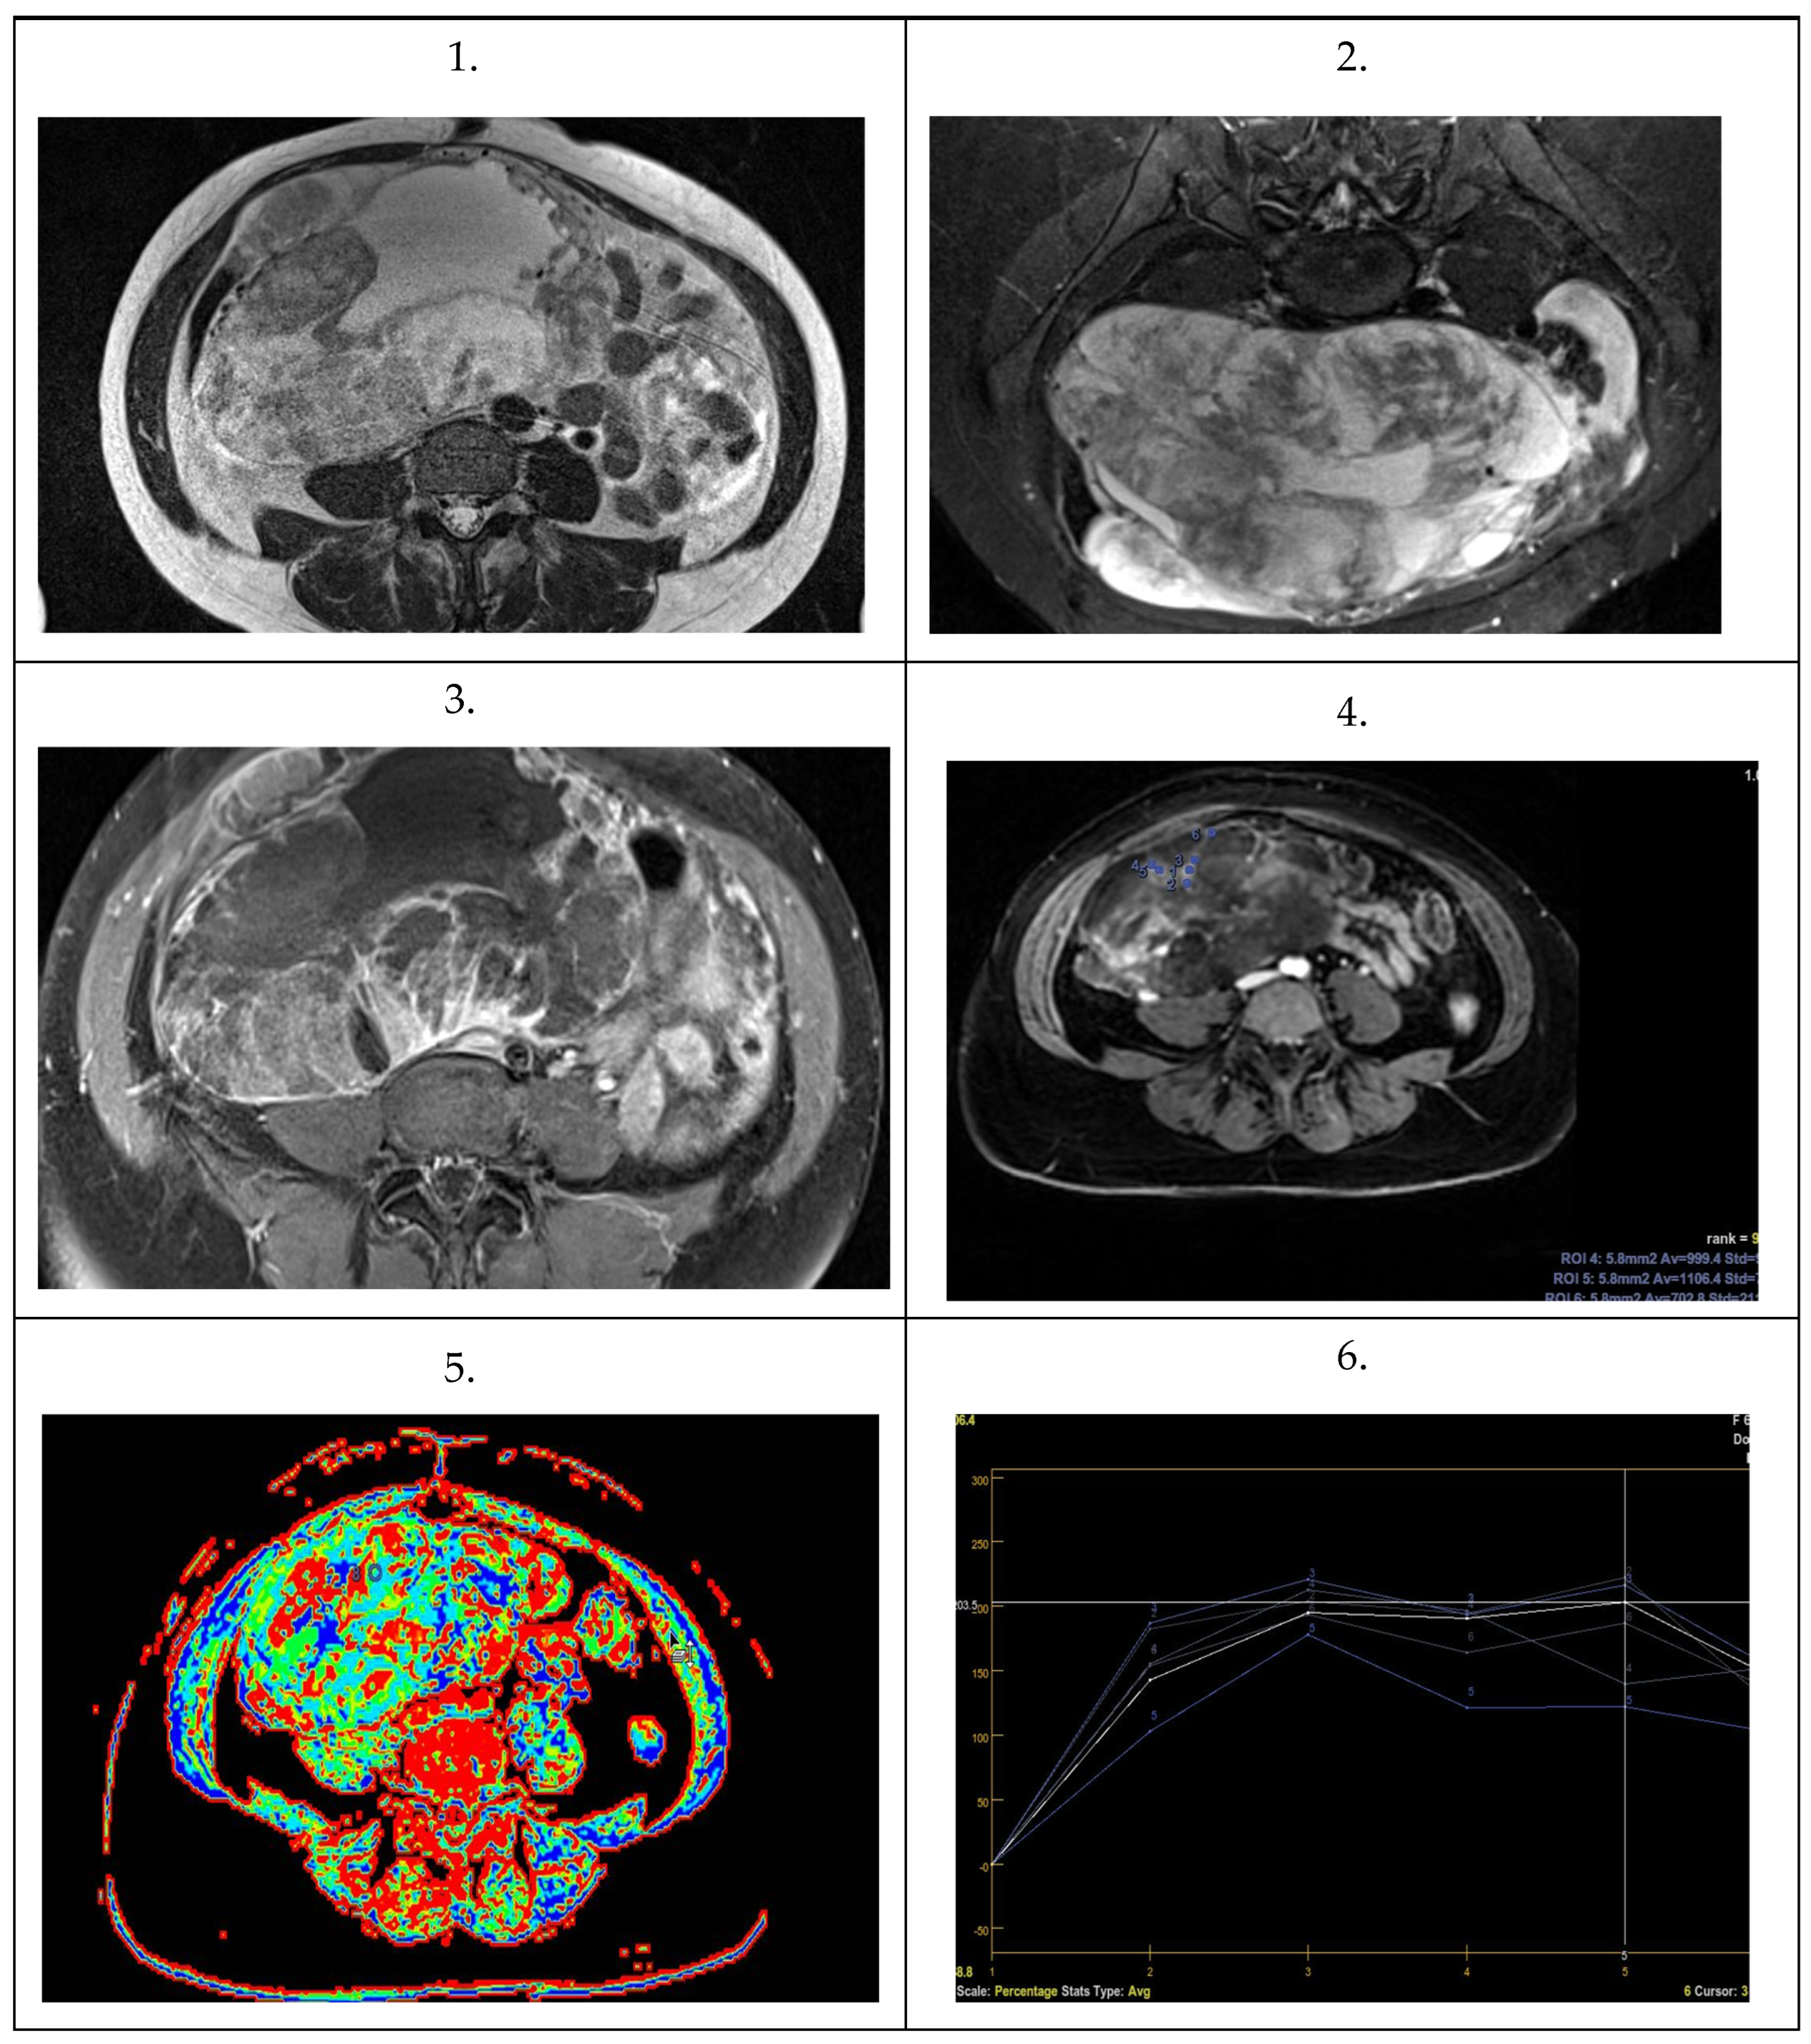

| Parameter | Statistic | Total | Primary Ovarian Cancer | Metastatic Ovarian Tumor | p Value |

|---|---|---|---|---|---|

| N = 57 | N = 10 | N = 47 | |||

| ADC 1 | Median | 851 | 1465.5 | 842 | 0.0001 |

| Q1–Q3 | 814–888 | 1430.5–1537.25 | 810.5–875 | ||

| ADC 2 | Median | 843 | 1434 | 821 | 0.0001 |

| Q1–Q3 | 800–890 | 1345.75–1643 | 800–872 | ||

| ADC 3 | Median | 846 | 1631.75 | 824 | 0.0001 |

| Q1–Q3 | 808–899 | 1400.5–1678.25 | 806–871.5 | ||

| ADC 4 | Median | 865 | 1442 | 845 | 0.0002 |

| Q1–Q3 | 811–998 | 1230.25–1627.35 | 809–895 |

| TTP | Median | 157 | 410 | 154 | 0.0001 |

| Q1–Q3 | 149–171 | 370–465 | 147.5–161 | ||

| Perf.Max En. | Median | 167 | 141 | 167 | 0.5 |

| Q1–Q3 | 143–193 | 135.25–198.25 | 145–189.5 |